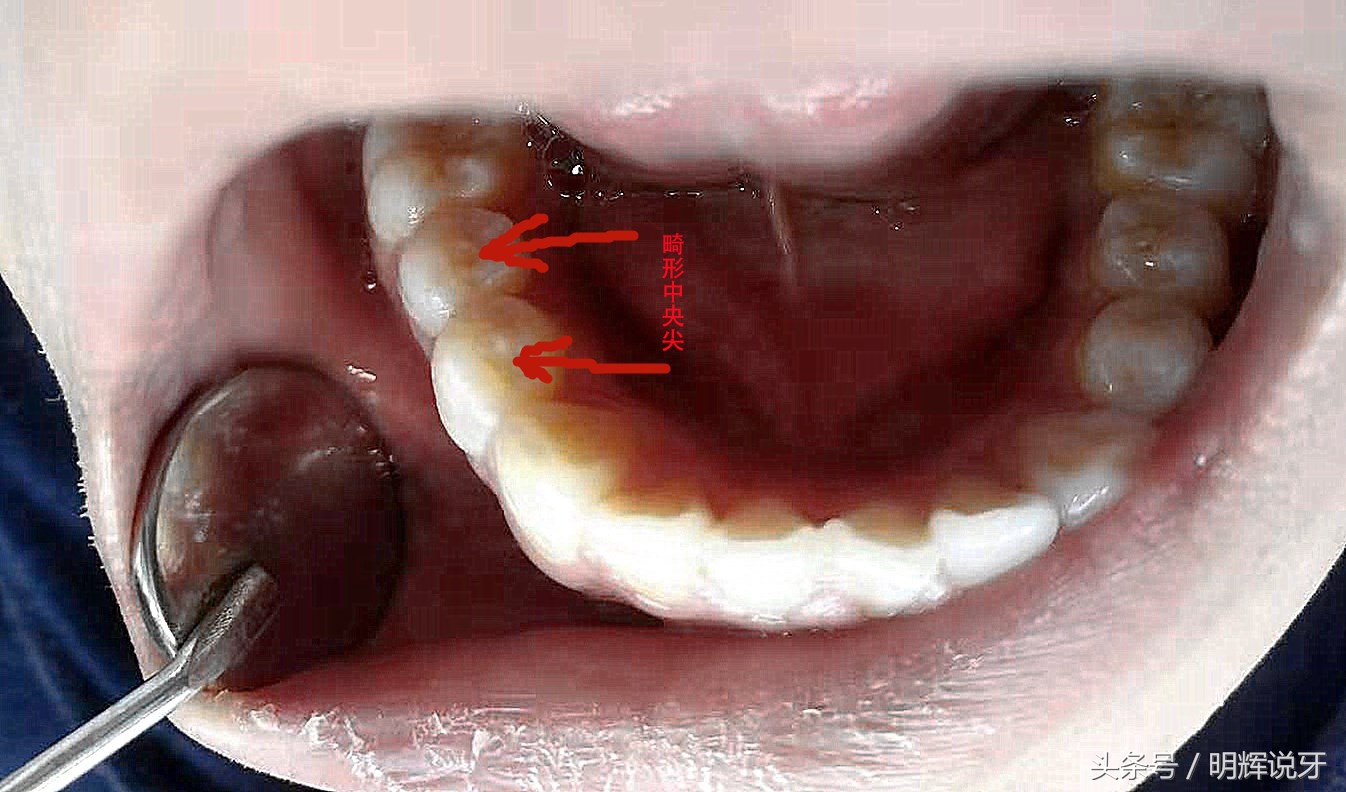

但是有些牙尖,让人烦恼,虽然你也不想见他,但是他确随你而来,你只能接受,因为他是天生的畸形,又称畸形中央尖,常见于前磨牙,突出在牙齿的最中间!

畸形中央尖

所以请各位有牙的人,回家后照照镜子,看看自己的前磨牙上有没有多余的牙尖?

多余的牙尖